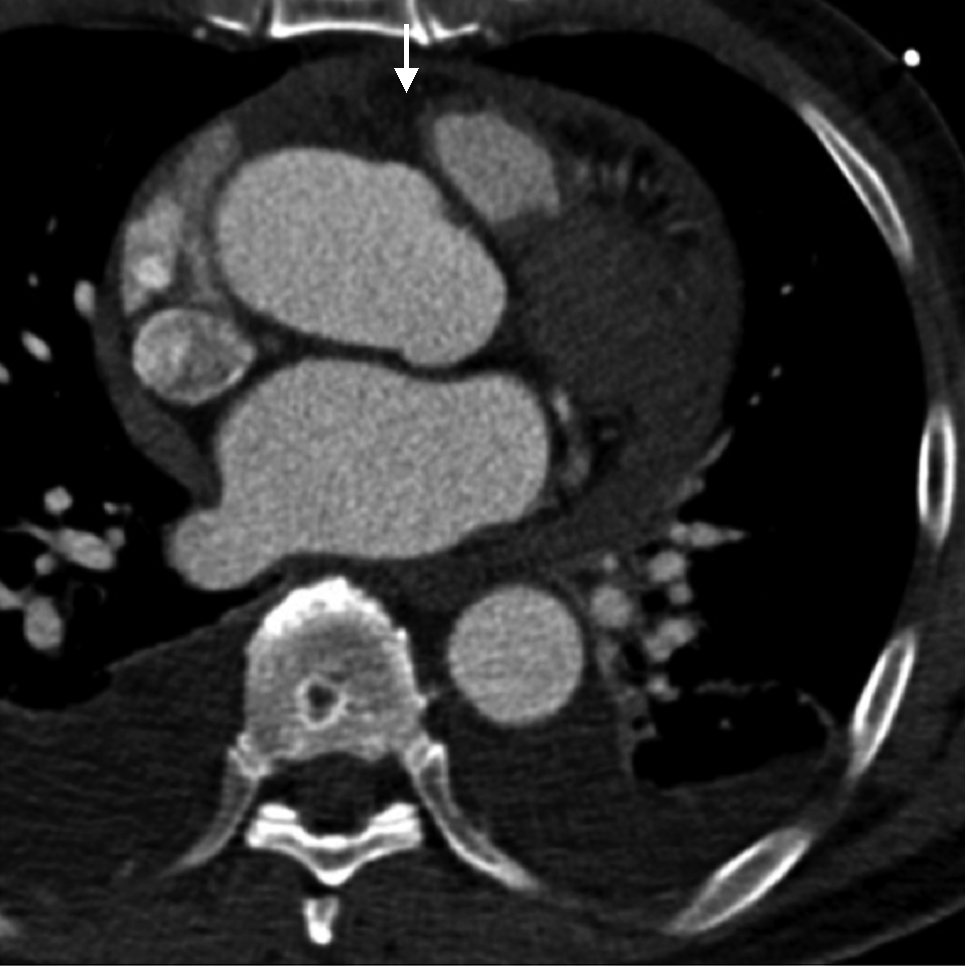

患者入院后血压逐渐恢复至140/85 mmHg,予络活喜控制血压及保肝治疗,患者肝肾功能逐渐好转。5月6日转至心外科全麻下行Bentall手术+主动脉瓣生物瓣置换术(图5)。术后回顾患者主动脉CTA,其主动脉根部冠脉窦水平可见夹层迹象(图6)。

入院后查ALT 1976 U/L,AST 713 U/L;复查主动脉CTA未见明确夹层。4月26日TEE示升主动脉根部左冠窦壁呈2条分离的回声带,腔内可见纤细的剥离的内膜片,起始于主动脉瓣左冠瓣根部,局限于主动脉窦管部。彩色及频谱多普勒显示:舒张期左室流出道内可见中等量五彩镶嵌的主动脉瓣反流束,同时可见少量血流通过升主动脉内膜破口进入假腔(图4)。诊断AD(Stanford A型),中度主动脉瓣关闭不全。